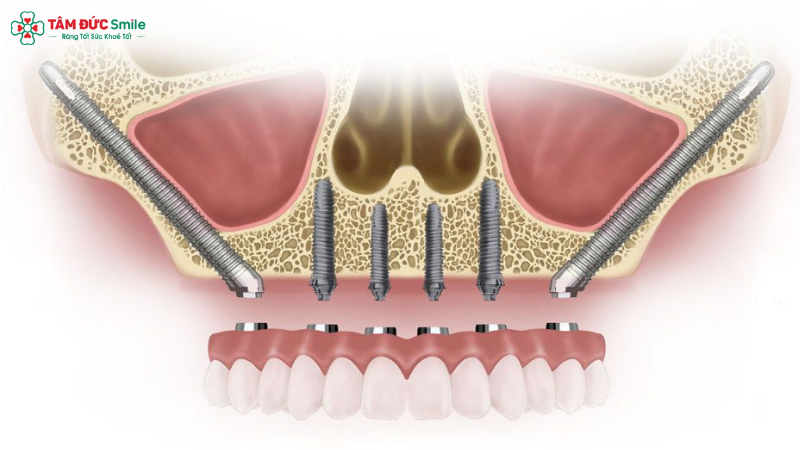

Zygomatic dental implants are a specialized form of dental implant therapy designed for patients who suffer from severe upper jaw bone loss and are not suitable candidates for traditional dental implants. Instead of being anchored into the maxillary (upper jaw) bone, these implants are placed into the cheekbone (zygomatic bone), which is significantly denser and more stable.

From a clinical perspective, the definition of zygomatic implants centers on their extra-long implant design. Unlike conventional implants that typically range from 8–15 mm in length, zygomatic dental implants can extend up to 30–55 mm. This extended length allows the implant to bypass the resorbed maxillary bone and gain firm anchorage in the zygoma, a strong facial bone that rarely undergoes resorption even in long-term edentulous patients.

3.2 Surgical Placement of Zygomatic Implants

During zygomatic implant surgery, the implants are placed through the upper jaw and anchored into the zygoma. The procedure is usually performed under general anesthesia or deep sedation and takes approximately 3 hours, depending on case complexity.

Key surgical characteristics include:

- Use of extra-long implants

- Angled insertion to maximize stability

- Avoidance of bone grafting

- Immediate or early loading possibilities

Thanks to the density of the cheekbone, primary stability is often excellent, allowing for immediate provisional restoration in many cases.

5.3 Full-Arch Rehabilitation Possibilities

Full-arch rehabilitation is one of the most common applications of zygomatic dental implants. By combining zygomatic implants with conventional implants in the anterior maxilla, clinicians can restore a full upper arch with a fixed prosthesis.